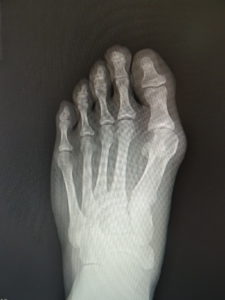

(図5)

手術前 手術後4年

(図6)

手術前 手術後

(図7)

真田理事長による手術の様子。外反母趾|症例 (左から 手術前、手術後、ワイヤ抜去後)